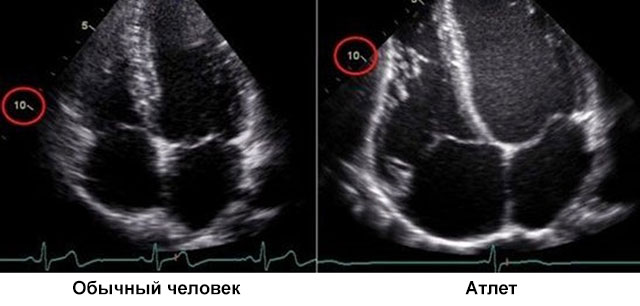

По значимости УЗИ сердца стоит на одной ступени с таким исследованиями как: ЭКГ, МРТ, КТ. В основе процедуры лежит свойство внутренних тканей отображать, рассеивать, поглощать ультразвуковые волны. С помощью специального датчика, волны направляются на исследуемый орган. Он же фиксирует отраженные и передает на компьютер. Обработанная информация отображается на экране в реальном времени. Это позволяет визуально осмотреть доступные части органа.

Исследование проводит врач, специализирующийся на УЗИ – сонолог. Во время процедуры оцениваются такие параметры, как:

1. Размер сердечных камер и толщина стенок;